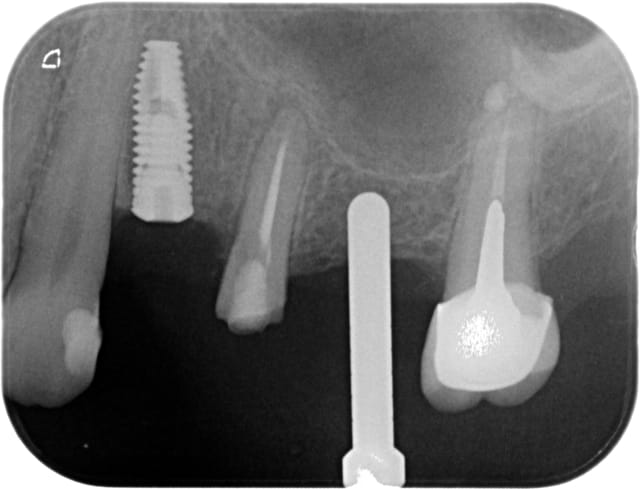

Voila je me lance, mais je n'ai que les RX.

24: largeur de crete 3mm, hauteur 9.8, j'ai placé un 3.75x10

26: largeur de crete 4mm, hauteur 4.7, j'ai placé un 4.2x7

A vos critiques et au plaisir de vous lire.

si oui, fais attention, çà déforme un peu les perspectives...donc peut fausser ton axe de forage (cf ton implant en 24 qui "louche" vers la 23...)

Pour pluton, ni loupes ni guide chir, à main levée... Mais je pense que ma prochaine chir se fera avec guide. L'implant 24 m'a un peu fait peur par sa proximité avec 23.